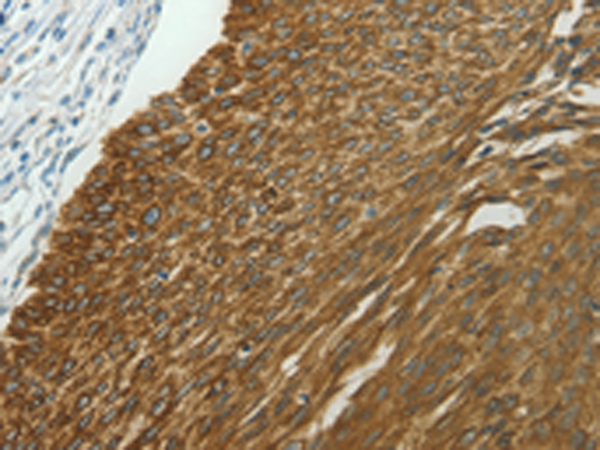

中文名稱: 兔抗NDRG2多克隆抗體

英文名稱: Anti-NDRG2 rabbit polyclonal antibody

ELISA, WB, IHC

IHC positive control:

Human liver cancer and Human lung cancer

IHC Recommend dilution:

25-100